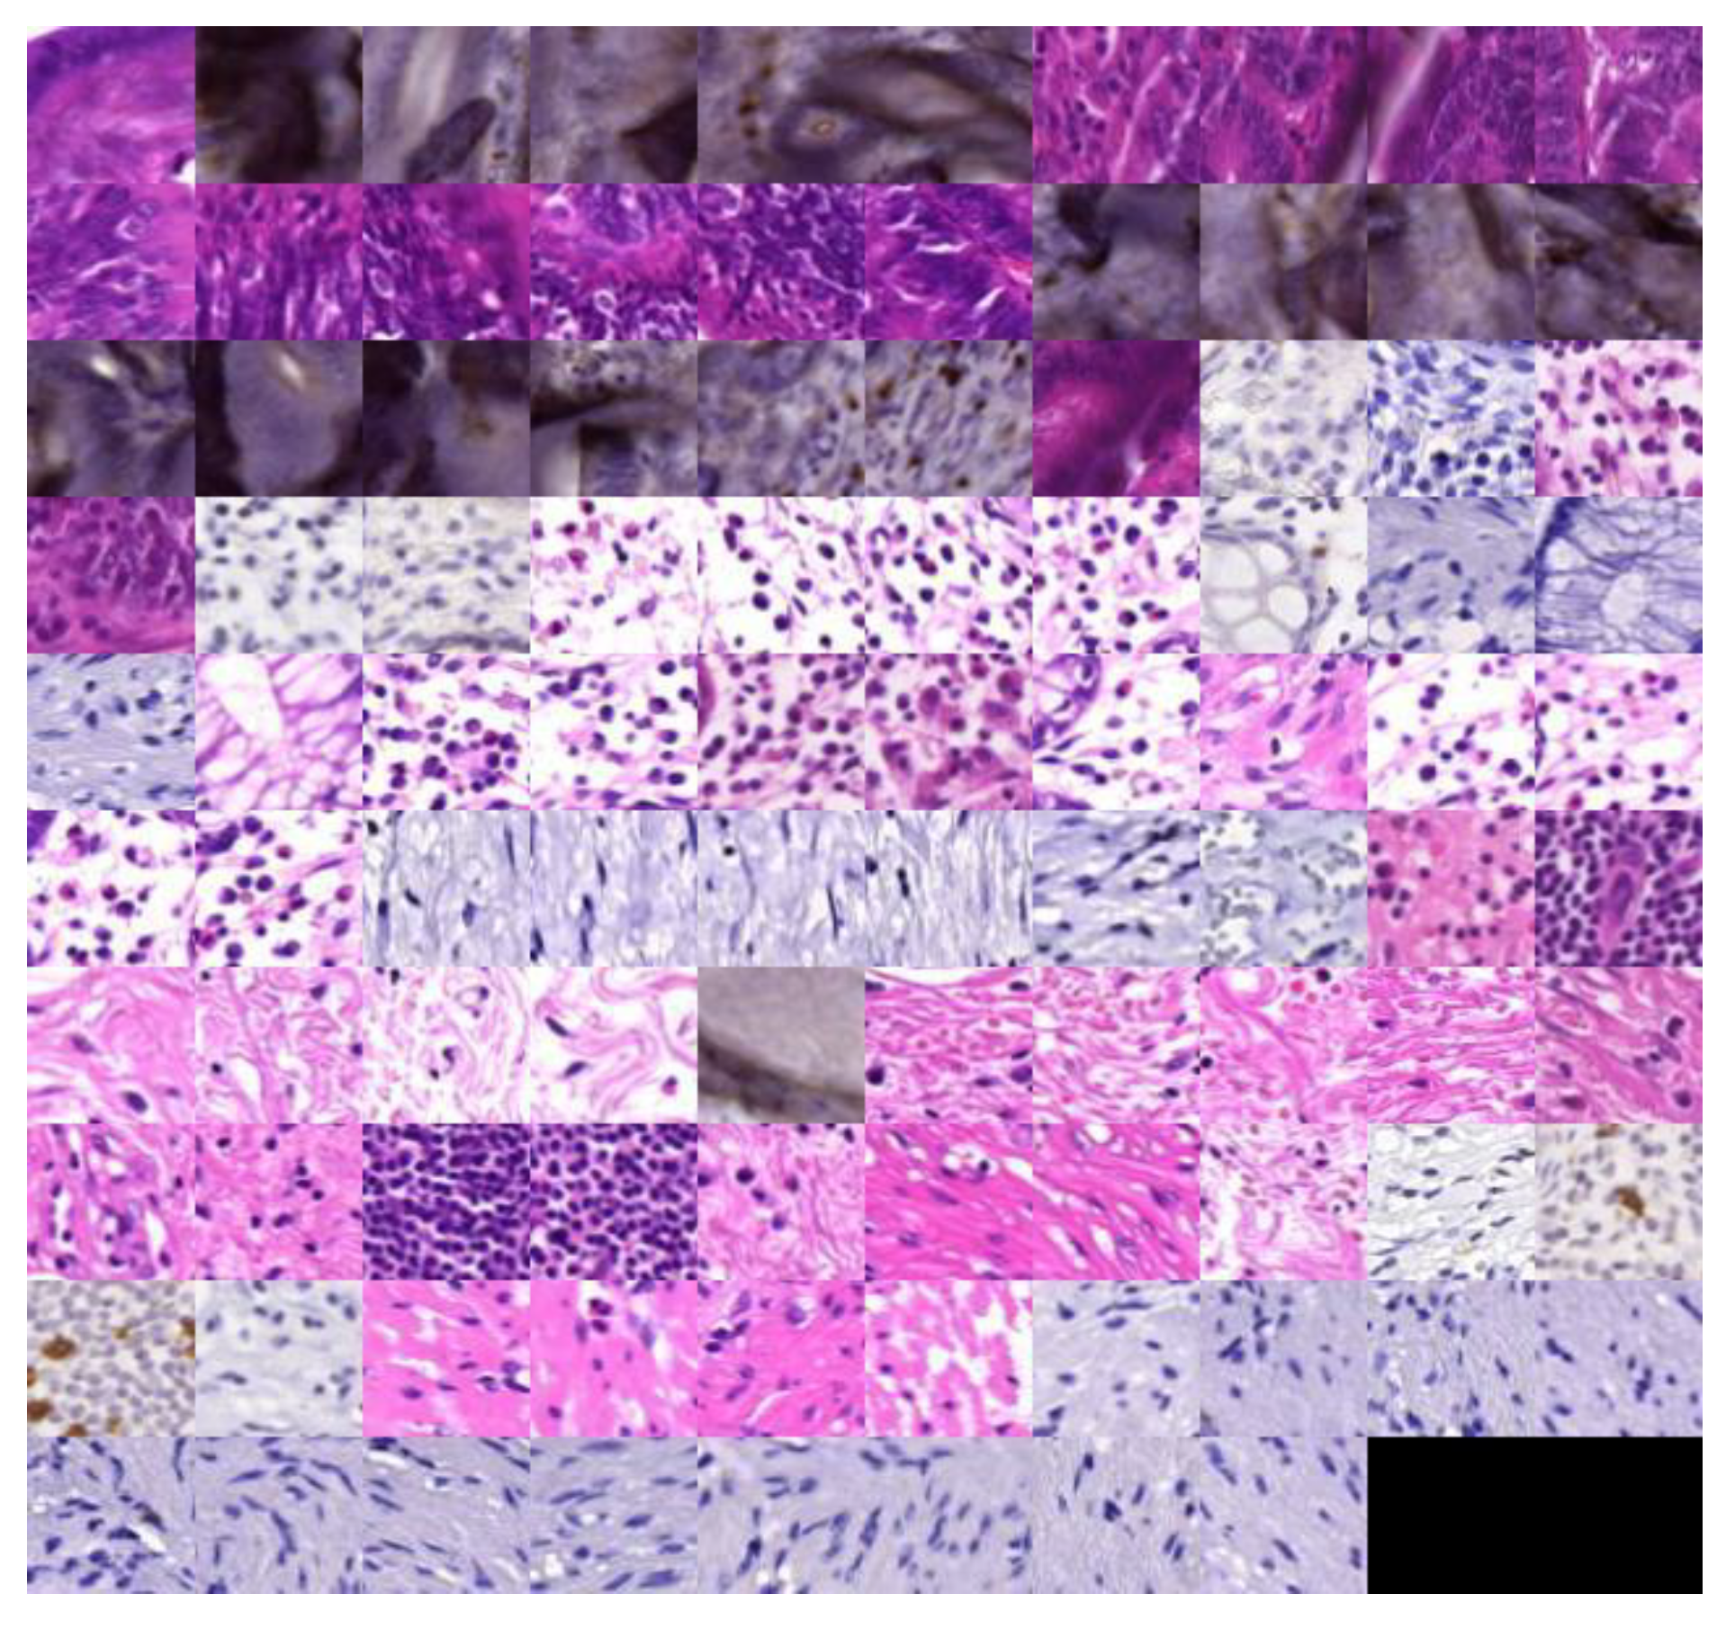

2.1. Materials

3.1. Latent Space Disentanglement